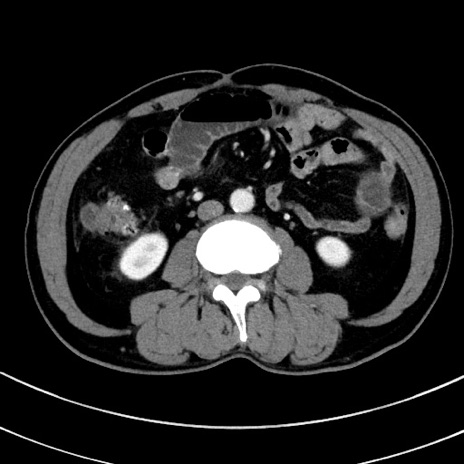

症例8(横断像)

【症例】 60歳代男性

【主訴】 黒色吐物

【現病歴】 4日前から嘔気自覚、2日前の朝食後にも嘔気あり、自分で手で嘔吐反射起こし嘔吐したところ血が混ざっていたため受診。

【既往歴】 5年前汎発性腹膜炎を伴う急性虫垂炎で手術、高血圧、前立腺肥大症、高脂血症

【身体所見】 腹部正中に手術癩痕あり 腹部平坦・軟圧痛なし膨満感あり

【データ】WBC 8400、CRP 4.54